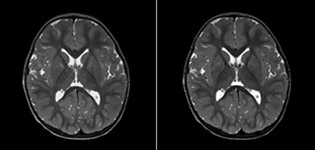

The value of susceptibility weighted imaging in visualizing brain injury is well documented. The Philips multi-echo SWIp technique provides fast susceptibility weighted imaging with enhanced susceptibility contrast and high resolution.

“SWIp helps us identify blood or blood products, calcification, and diseases that affect the vascular system,” says Dr. Miller. “In children with traumatic brain injuries, it highlights areas that are injured, better than some of the previous techniques that we were using. These children often have micro-injuries that cause small amounts of blood or tissue damage. Adding SWIp helps us to better characterize the extent and nature of the injury. Having characterized an injury to the extent of what’s possible supports our diagnostic confidence.”

“I would definitely recommend other users to implement SWIp. We initially added the SWIp sequence following a lot of support for its utility in the literature. Then we directly compared SWIp to the 2D gradient echo sequences that we were using. After a good amount of clinical experience in seeing its benefits, we were confident to replace the old sequences with SWIp. It gives us a better assessment of the physiological processes of the brain that were less apparent on our previous imaging sequences,” says Dr. Miller. “SWIp is now a routine sequence for imaging traumatic brain injury patients at PCH, and it’s episodically added for patients who have intracranial vascular abnormalities.”

“I believe SWIp is rapidly becoming the standard in imaging traumatic brain injury, because of its high sensitivity to venous blood products. SWIp may even help attract patients; our neurosurgeons often ask to have the patients imaged on our scanners with highly sensitive techniques like SWIp. There’s also a growing application of SWI sequences in other vascular abnormalities because of the possibilities around physiological assessment of the brain than just a standard structural imaging.”